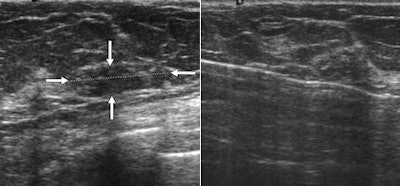

| Ultrasound image (left) reveals subtle, hypoechoic, ovoid-shaped, 2-cm mass (arrow) containing numerous echogenic foci. Ultrasound-guided needle core biopsy image (right) reveals LCIS. At open surgical biopsy, diagnosis of infiltrating lobular carcinoma was made. |